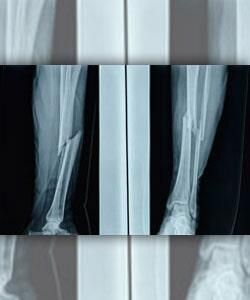

Como médico traumatólogo se especializa en cirugía de columna vertebral, y ofrece los mejores cuidados ante deformidades, escoliosis, pie plano, hernias de disco, fracturas y otros problemas en esa área.

- Fracturas